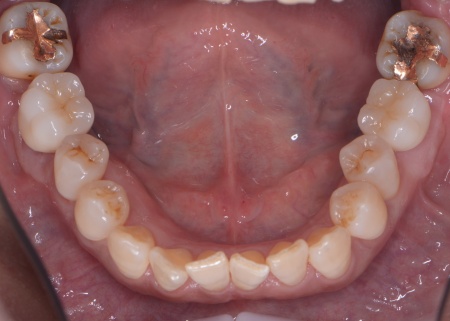

| カウンセリング | 拝見したところ、上下左右の奥歯計8本(第1大臼歯、第2大臼歯)に重度の歯周病が認められました。 歯周病は歯を支えている骨や歯ぐきに炎症が起こる病気です。進行すると歯がぐらついたり、噛む力が弱くなったりします。 さらに悪化すると歯を失う可能性が高くなるだけでなく、周囲の歯にも影響が広がることがあります。 特に下の奥歯2本(左右第1大臼歯)は歯を支えている骨が著しく減少して歯が大きく揺れており、治療して温存することは難しい状態でした。 また、左上の奥歯(第1大臼歯)は過去に詰め物で治療されていましたが、その下で虫歯が再発しています。 以上のことから、下左右の第1大臼歯は抜歯後に歯を補う治療、その他奥歯の治療、再発した虫歯の治療が必要と診断しました。 |

さらに虫歯が再発していた左上奥歯については、虫歯をしっかりと取り除いたうえで被せ物による修復治療を提案しました。 それぞれのメリット・デメリットを丁寧に説明したところ、治療計画に同意いただきました。 まず、歯周基本治療から開始しました。 下左右の第1大臼歯を抜歯し、その部位にインプラントを埋め込む手術を行いました。同時に、インプラントの隣にある下の第2大臼歯に対して歯周組織再生療法を施しています。 また、左上の奥歯は虫歯を取り除いたあと、歯の形を整えて型取りを行い、最終的にジルコニアクラウンを装着しています。 段階的に治療を進め、すべての治療を終了しました。 |